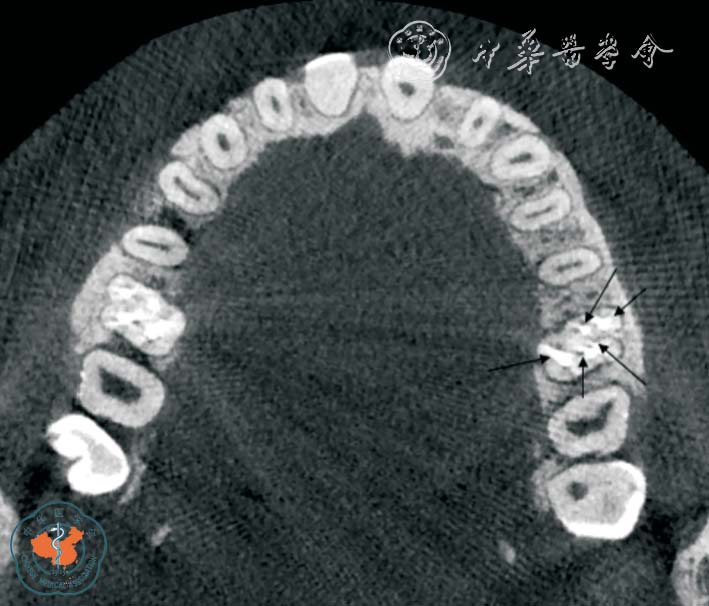

1. 正确判断根管数目: 根管数目的正确判断是根管治疗成功的主要因素之一。 Baratto Filho 等11采用体外研究、临床研究和CBCT 三种方法分析了上颌第一磨牙的根管解剖。 体外研究表明,140 颗离体牙中67.12%存在第四根管,其中1 例有7 个根管,存在第四根管的磨牙中92.58%第四根管位于近中颊根。 临床研究表明,53.26%及0.35%的磨牙分别存在4、5、6 个根管, 并且95.63%发生于近中颊根。 CBCT 研究表明,1.85%、37.05%、1.85%的磨牙分别存在2、4、5 个根管。 同时CBCT 对变异根管的发现和定位具有重要意义。 临床医师在根管治疗术前及术中可随时调用和调整CBCT 局部三维重建图像,从不同角度及层面观察根管的融合和分支情况,了解根管的形态、数目、走向、根尖处根管的位置是否融合等,是指导复杂根管系统牙齿治疗时的重要影像手段(图1 ~2)。

图1 CBCT 轴位显示左上颌第一磨牙5 个根管,其中侧支根管未根冲